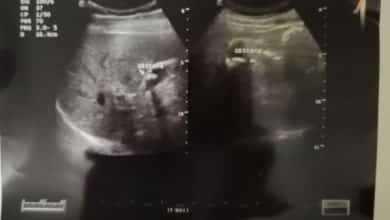

تقرير عن الكبد

liver:is of average size 16 cm showing uniform hyperechoic parenchymal echopattern no dilated intrabiliary radicles normal pv